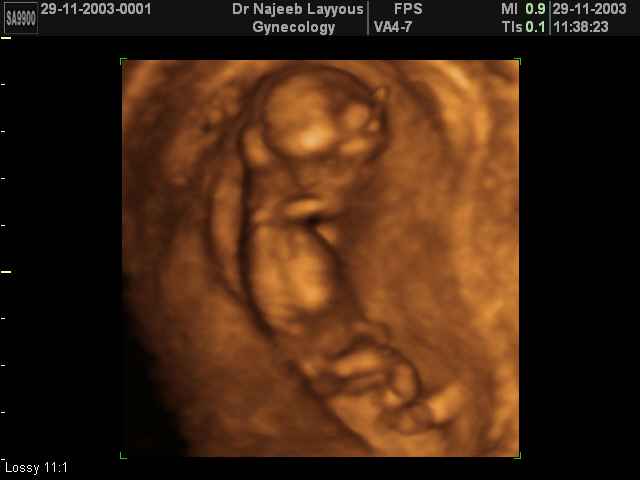

3D First Trimester Ultrasound Scan Photos